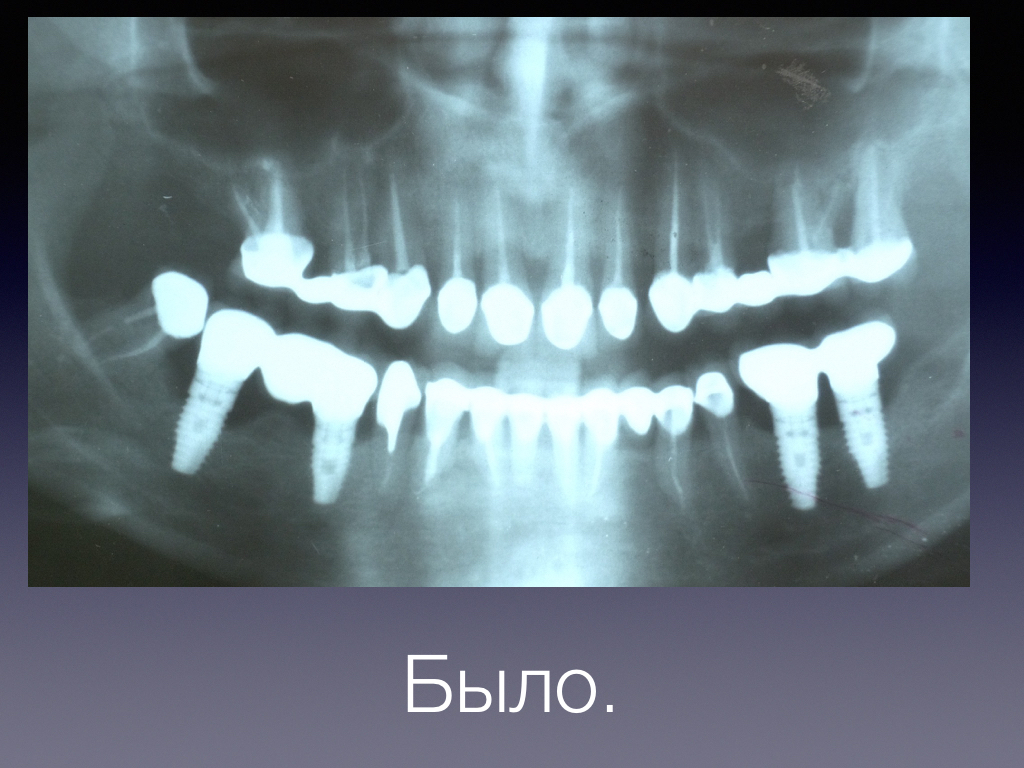

Периимплантит и БИОИМПЛАНТ ГАП -ОБНОВЛЕНО